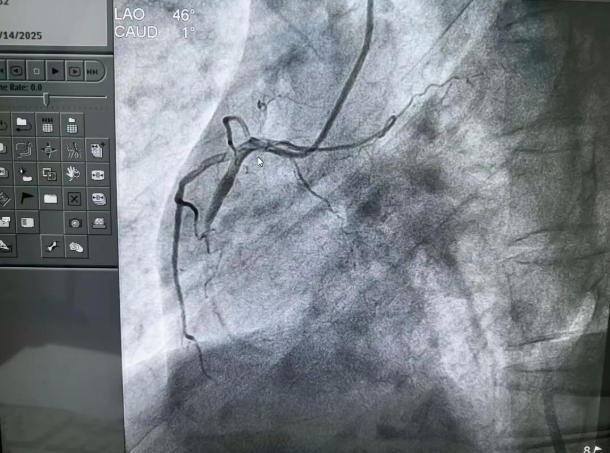

▲术前